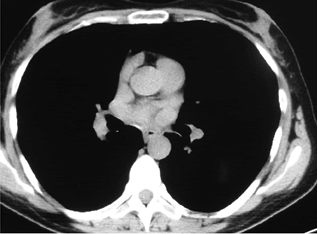

Electromyography showed low amplitude of compound muscle action potential (CMAP), decremental responce at lowrate repetitive nerve stimulation (2-5 Hz) and marked incremental responces at high-rate nerve stimulation (50 Hz), changes characterized by the myastenic syndrom. It was made a new CT of lung and mediastinum (native), which showed a huge paracardial soft-tissue multilobulated mass (7sm in diameter) with finny spicules with central localization in the right lung, compressing middle and lower lobe bronchi (Figure 2).